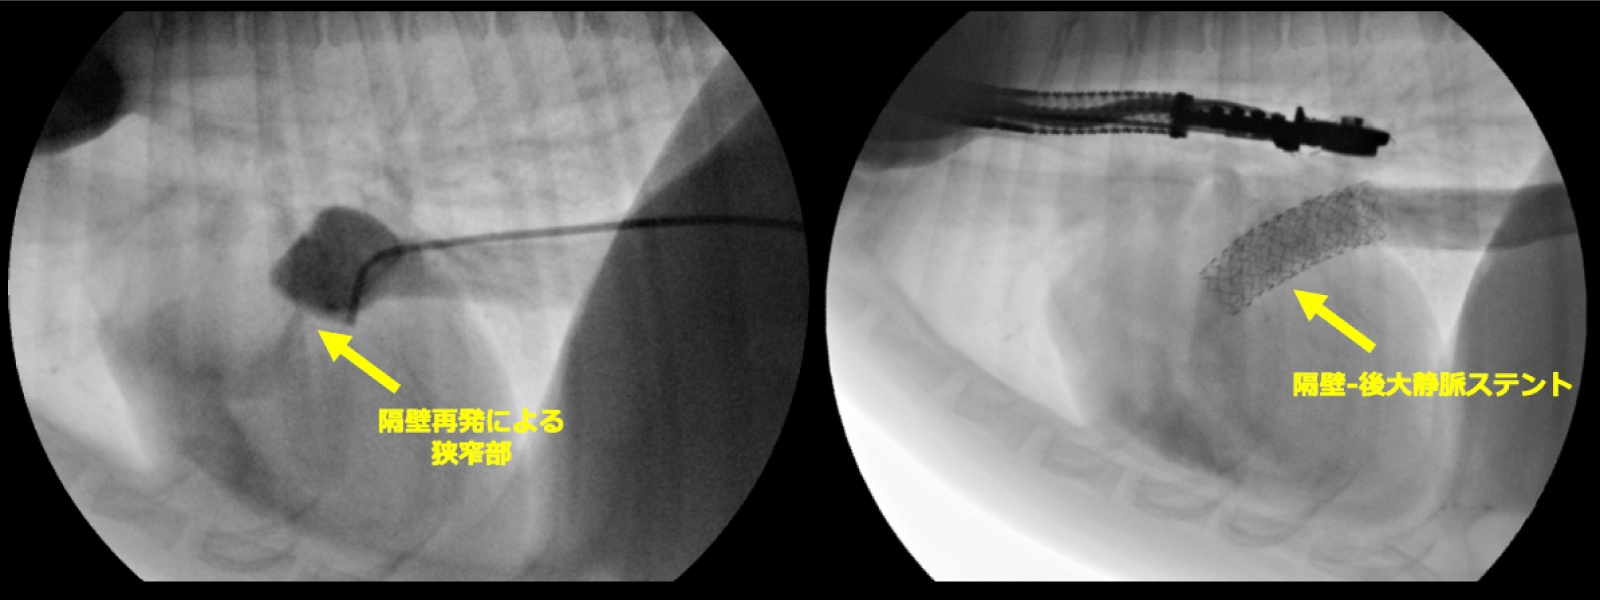

異常隔壁を全て除去することで隔壁孔を

4.3mm→9.0mmに拡張

ステント留置後、臨床症状の改善を確認